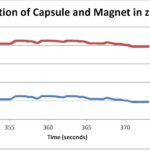

Development of Withdrawal Algorithm for Capsule Endoscopy in Research and Clinical Setting

An algorithm was developed to autonomously control the capsule endoscope, allowing doctor to focus on diagnosing the patient.

Posted by Greta Clinton-Selin on Wednesday, May 24th, 2017 in May 2017, Endoscopy, external magnet, nanotechnology, python, simulation